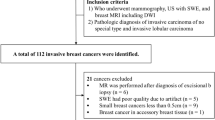

This retrospective study was approved by our institutional review board, which waived the requirement for informed consent. From June 2016 to January 2018, 475 consecutive women with suspicious breast masses, which were assessed as category 4 or 5 according to the Breast Imaging Reporting and Data System US lexicon [25], underwent B-mode US and SWE before US-guided tissue diagnosis. Of 475 patients, 82 patients who were identified with pathologically invasive breast cancer and underwent surgery without neoadjuvant chemotherapy were included in this study (Fig. 1). The mean age of the patients was 53.9 years (range, 36─85 years). Three hundred ninety-three patients were excluded for the following reasons: (a) the pathology diagnosis was benign tumor (n = 340) or ductal carcinoma in situ (n = 24), (b) neoadjuvant chemotherapy was performed before surgery (n = 23), (c) the patient was not treated in our hospital (n = 3), or (d) the SWE image quality was not suitable for evaluation (n = 3).